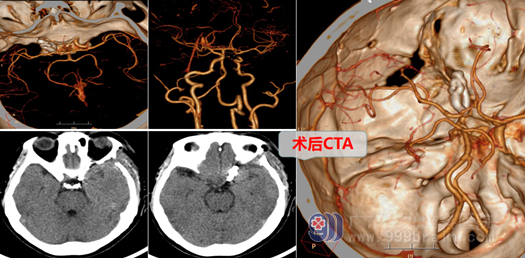

在完善相关检查后,外十科主任欧阳辉教授组织进行了详细的术前讨论,邓心情医师向家属交待了病情,说明手术的必要性和手术风险,在取得病人及其家属理解并签字同意后,外十科团队在全麻下为黄阿姨进行了左侧颈内动脉眼动脉段动脉瘤夹闭术。全麻成功后,取左侧翼点入路,咬除部分蝶骨嵴,从硬膜外细心暴露并磨除前床突,再剪开硬膜,在高清显微镜下释放侧裂池脑脊液,显露左颈内动脉、视神经,在床突段可见宽颈囊性动脉瘤,锐性分离动脉瘤周围粘连,暴露并保护动脉瘤,充分显露动脉瘤颈后精准地用动脉瘤夹将其夹闭,检查周围动脉保护完好,载瘤动脉通畅。手术顺利,麻醉满意,出血不多,术后病人全麻清醒,安返病房。

术后第3天,医生已拔出黄阿姨头部引流管及尿管,黄阿姨可正常饮食、下床活动,无任何不适,黄阿姨很开心以后终于不用害怕颅内“不定时炸弹”爆炸了,也不用忍受长期的头痛折磨了。